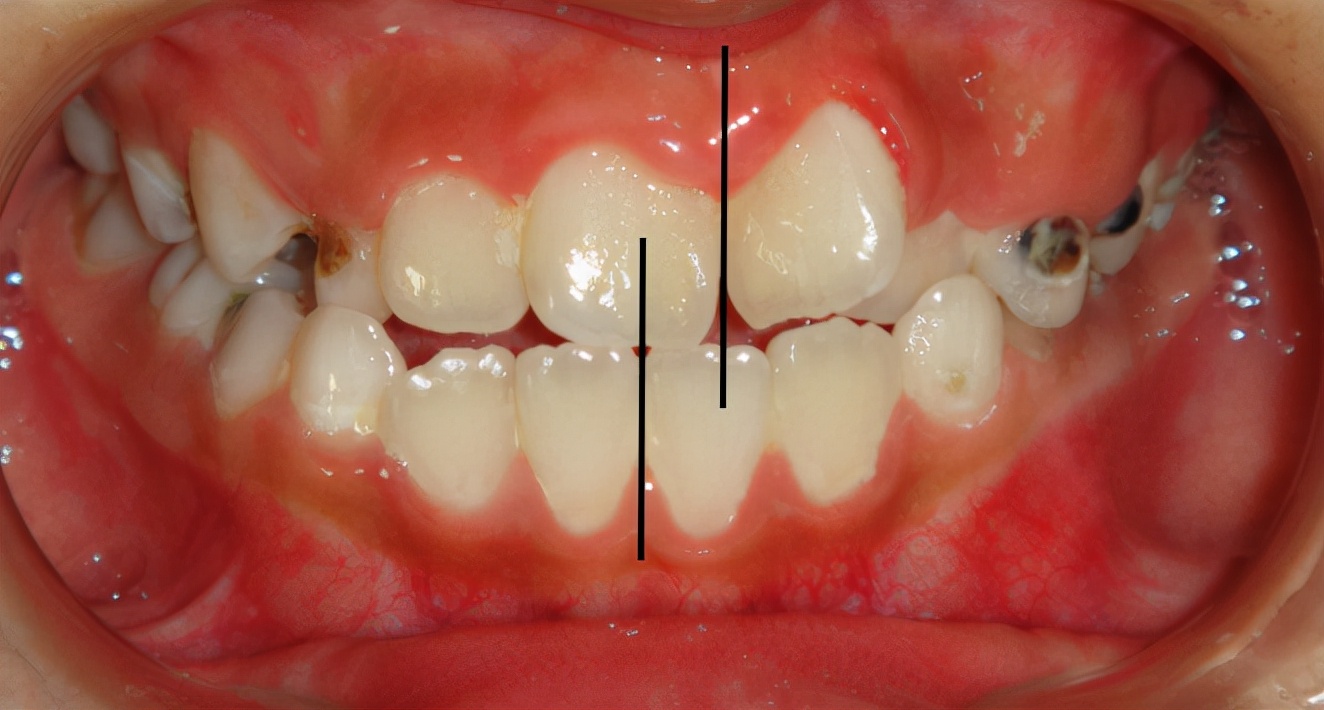

患儿的面像、口内情况如图所示。

可以看到患儿的下巴是偏斜的,面部不对称。经检查发现患儿口内可见多颗乳磨牙龋坏,有偏侧咀嚼习惯,存在颌骨发育的不对称。这种严重的骨性畸形需要双期矫治。第一期早期矫治,其目的是去除病因及干扰因素,让上下颌骨的生长导向正常,从矢状向、横向、垂直向去改善上下颌骨的不调。该患儿首先应用的是矫形力矫治器(螺旋扩弓器),协调上下颌骨宽度,去除锁合侧咬合干扰,建立双侧后牙咬合,治疗乳磨牙龋坏,同时指导患儿用双侧咀嚼食物促进咀嚼肌平衡发育。然后应用的是FRⅢ功能矫治器,解除前牙反合改善下颌偏斜,FRⅢ的作用原理是去除导致颌骨畸形的功能因素而且可以改善轻度的骨性错合。

下图为早期矫治前后面型和口内像对比,可以看到矫治后的患儿面型左右基本对称,下牙列的偏斜程度也明显改善,前牙的反合得到解除,去除了上颌骨发育的不利因素。接下来就是等待患儿换完牙以后进行二期治疗,二期治疗可以从三维方向上控制牙齿的移动方向,进一步平衡咬合,使得矫治效果更加稳定。二期治疗的矫治器可以选择固定矫治器也可以选择无托槽隐形矫治器。